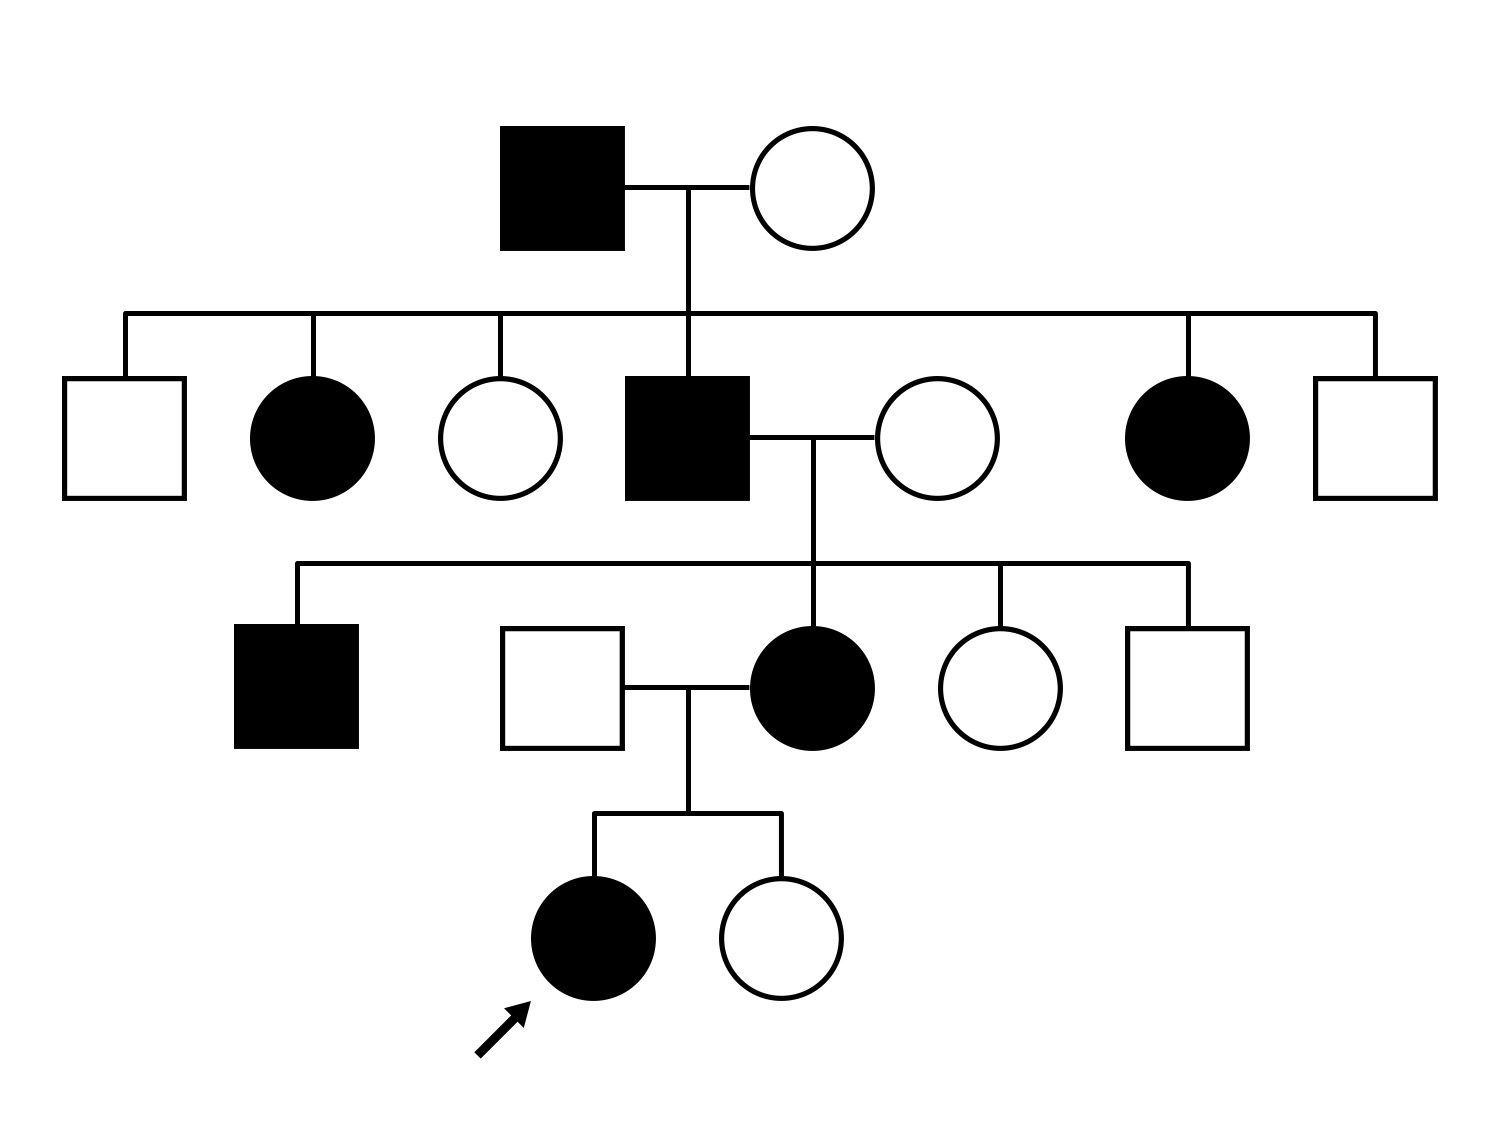

Malattia Leventinese (IIJ)

Malattia Leventinese (IIJ)

Diagnosis & molecular findings

| Disease | Gene | Allele 1 variant(s) | Allele 2 variant(s) | Inheritance mode |

|---|---|---|---|---|

| Malattia Leventinese | EFEMP1 | Arg345Trp CGG>TGG | AD |